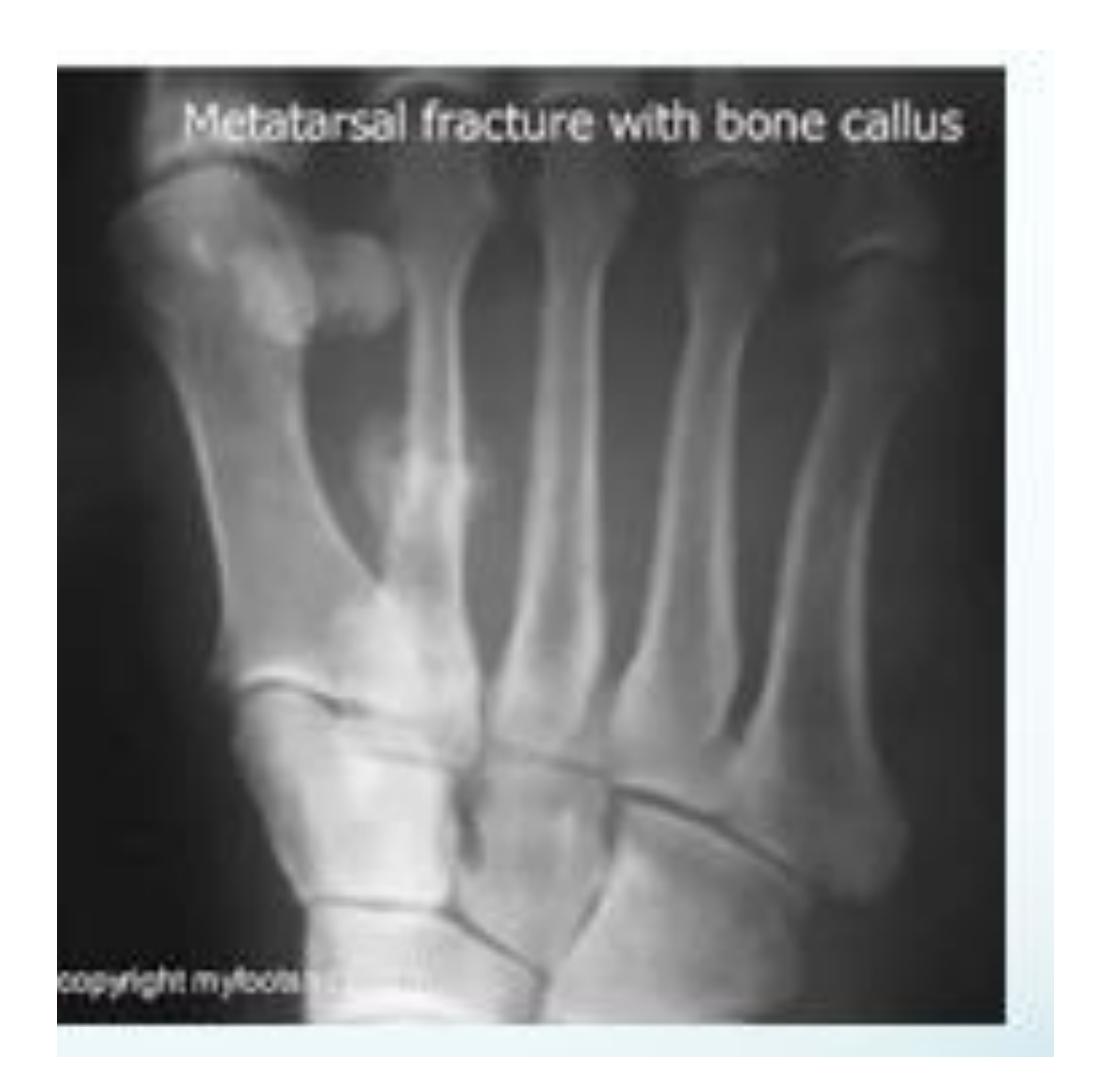

Stress Fracture Example

- Callous formation is 2nd metatarsal

- Looks like stress fracture